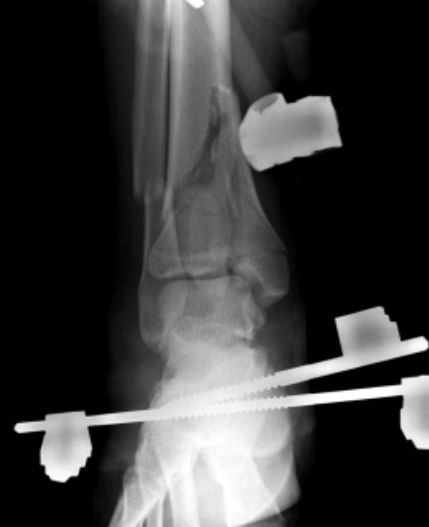

A 52-year-old carpenter falls off of a balcony while at work and sustains the injury shown in Figure A. The patient’s BMI is 52 and he smokes 2 packs of cigarettes per day; a clinical photograph of the limb is shown in Figure B. What is the most appropriate next step in management?

closed reduction

Ex Fix

ORIF later on when swelling settles